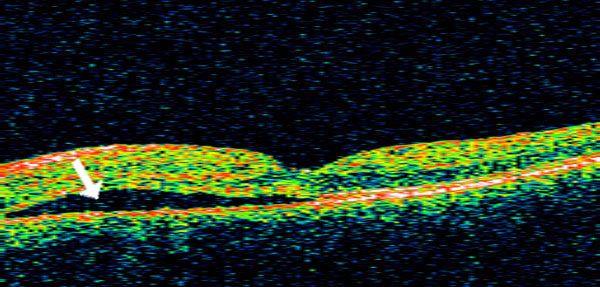

Macular Holes

The round shape of the eye is maintained by vitreous, a substance with the consistency of soft gelatin that fills the central eye. With age, the gel shrinks and shifts toward the front of the eye, pulling away from the surface of the retina. The body replaces the lost gel volume with natural fluid. For most people, the process presents no serious consequences beyond developing a few floaters. For a few, however, the attachment of the vitreous to the retina may be strong enough that the pull of the contracting vitreous can create a hole in the central retina, known as a macular hole. The replacement fluid may seep through the hole, lifting the retina and causing distortion in central vision.

A macular hole can develop as a result of pressure from the vitreous.

A macular hole causes decreased central focus for both near and distance vision, and a loss of vision in a small central area. To confirm a macular hole, Dr. Parks will perform a detailed retinal examination. This may include a fluorescein angiogram, in which photographs are taken of the back of the eye after a special dye has been injected into the blood.